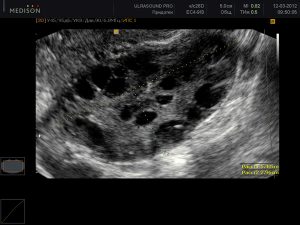

Непригодившийся фолликул заполняется жидкостью и остается внутри яичника. И так происходит каждый цикл на протяжении всего времени течения болезни. Можно представить, что вскоре будет с яичником, он превратится в скопление водянистых кист. Это и есть поликистоз яичников.

- Назначается УЗИ, на котором полностью обследуются органы малого таза.